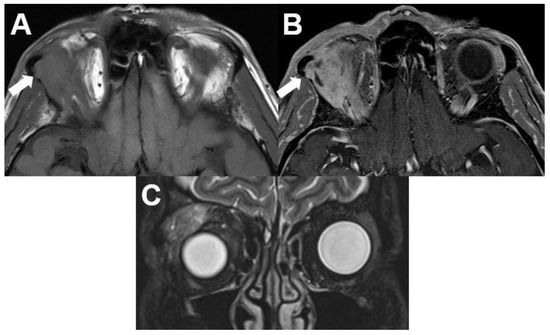

3.6. Masses with Involvement of Different Parts of the Orbit

3.6.1. Metastasis

3.6.2. Rhabdomyosarcoma